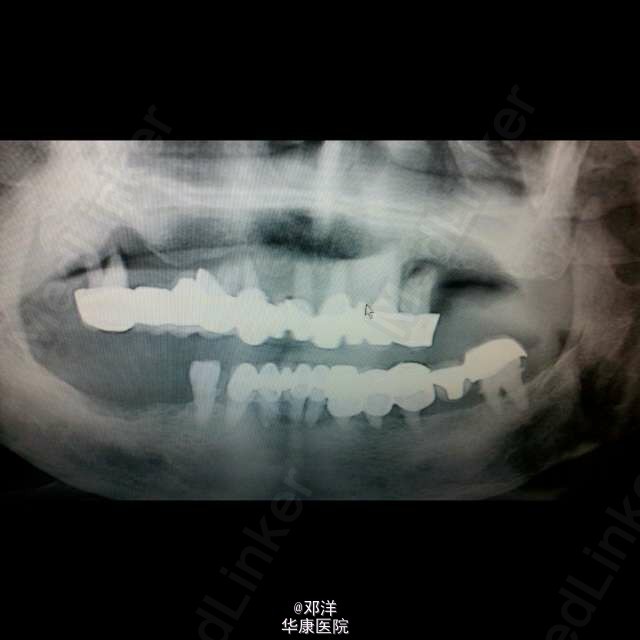

一份爱可以有多久,一座桥可以有多长~~最后只留了一颗